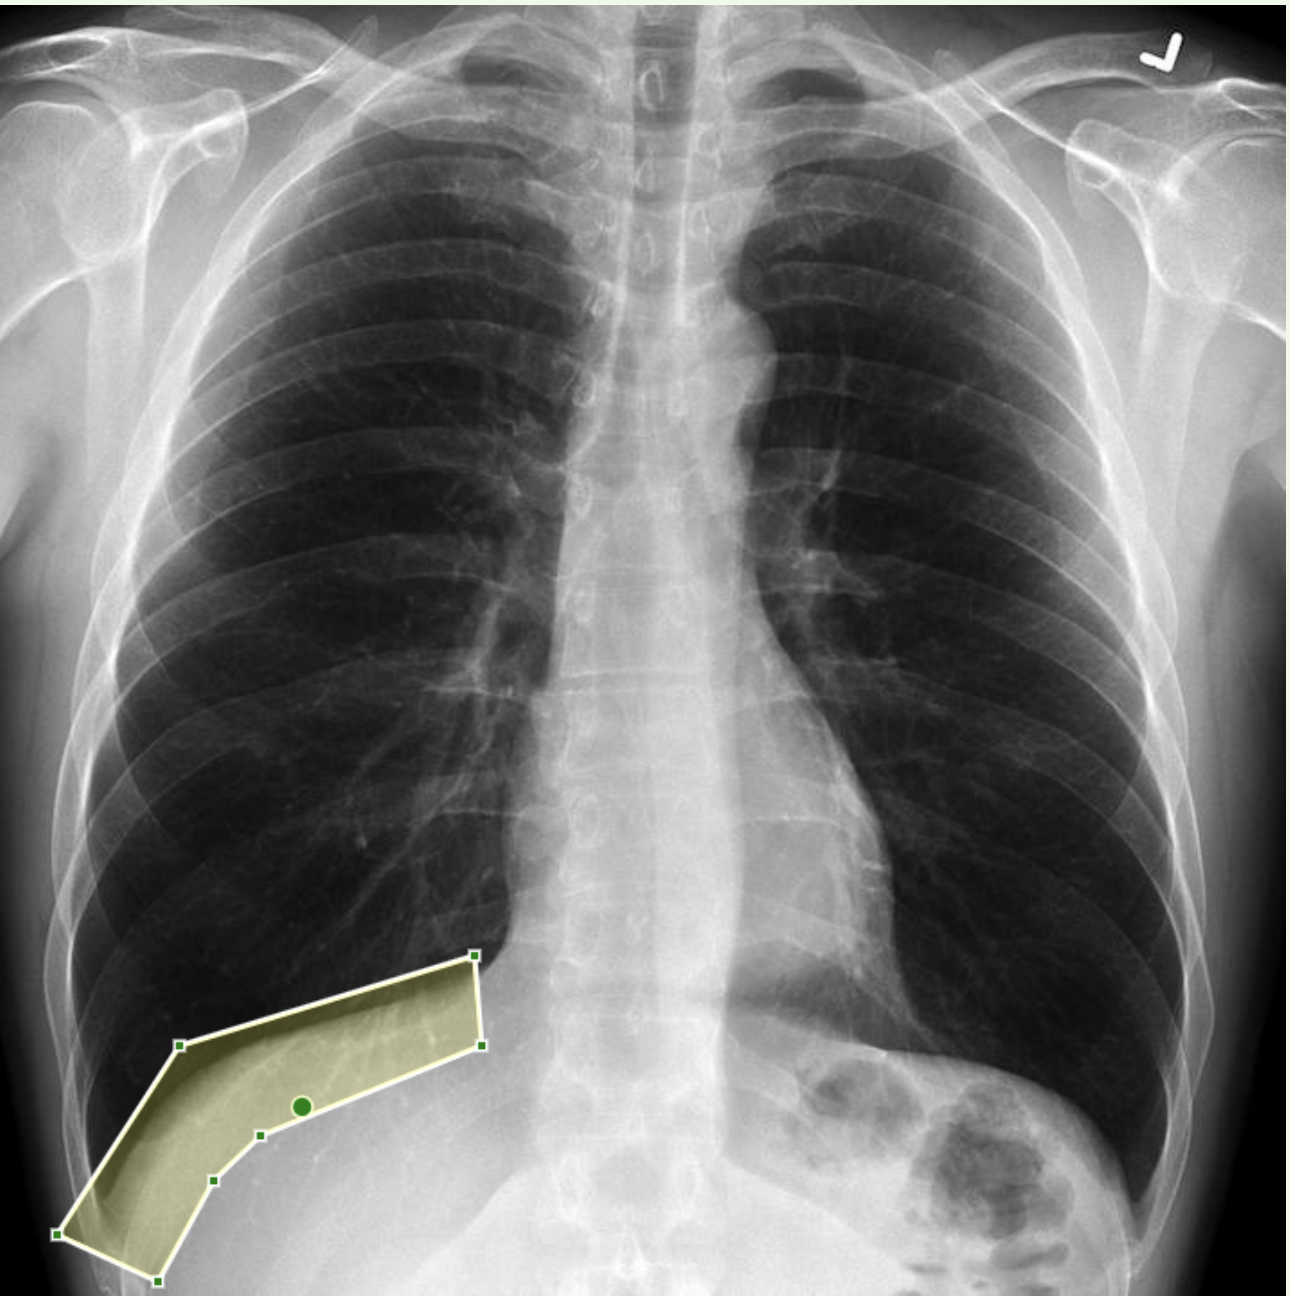

What is being shown here?

**Answer: Bowel wall inflammation** ## Footnote The descending colon is featureless with loss of the normal haustra. The right radiograph shows the inflamed bowel marked in green and the bowel wall thickening marked in light green. (You can also see an umbilical piercing.)